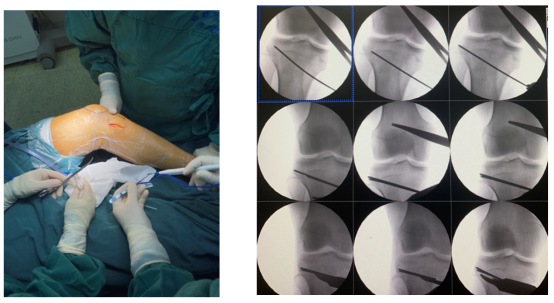

经过关节外科团队严谨的术前准备后,于术中确认合适的截骨平面,C型臂下透视测量下肢外观恢复变直,确保受力均匀,安放接骨板,反复确认力线......经过2个多小时的努力,顺利完成手术。

△术中

△术前、术后对比